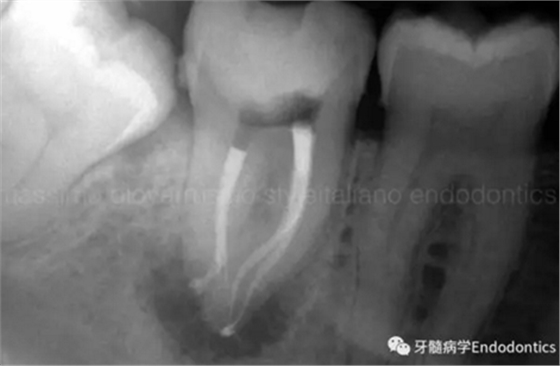

圖6.術(shù)后X線片顯示在根管機(jī)械預(yù)備后保留了原始的根管解剖形態(tài)結(jié)構(gòu)。冠方預(yù)敞和探查保證了對整個根管解剖形態(tài)結(jié)構(gòu)的保護(hù)。

圖11.術(shù)后X片顯示完成了根管的三維充填并很好地保留了復(fù)雜的解剖形態(tài)結(jié)構(gòu)。